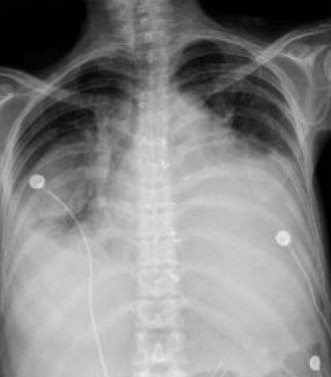

âȘ Table 7: We visualize samples of the generated reports for three cases. We bold the identical descriptions, underline the additional identified findings, and in red the failure findings.

X-ray Image | French Ground Truth | Our Generated Report | Translated to English | English Ground Truth |

![]() |

Opacité arrondie, de tonalité hydrique, bien limitée au niveau des tiers inférieur./ Moyen de l'hémichamp pulmonaire gauche./ |

CardiomĂ©galie associĂ©e Ă un infiltrat interstitiel origine infectieuse, Ă confronter au reste du bilan./ Ăpanchement pleural gauche de abondance./ |

Cardiomégalie associated with an interstitial infiltrate of infectious origin,to be compared with the rest of the assessment, abundant left pleural effusion./ |

Rounded opacity, watery in tone, well limited, at the level of the lower and middle thirds of the left pulmonary hemifield./ |